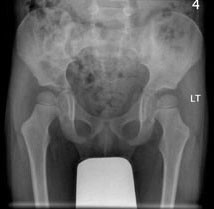

男,请根据其正常骨盆影像图像,判断其最可能的年龄 ( ) WXJ-0857.jpg

• A.7岁左右

• B.1岁左右

• C.10岁左右

• D.13岁左右

• E.4岁左右